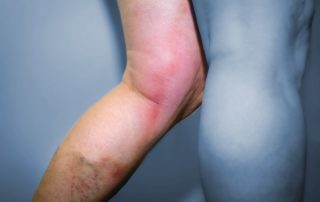

Vein Care Delivered To Your Home: In-home ultrasound diagnostics

Enjoy a thorough vascular assessment from the convenience of your own home.